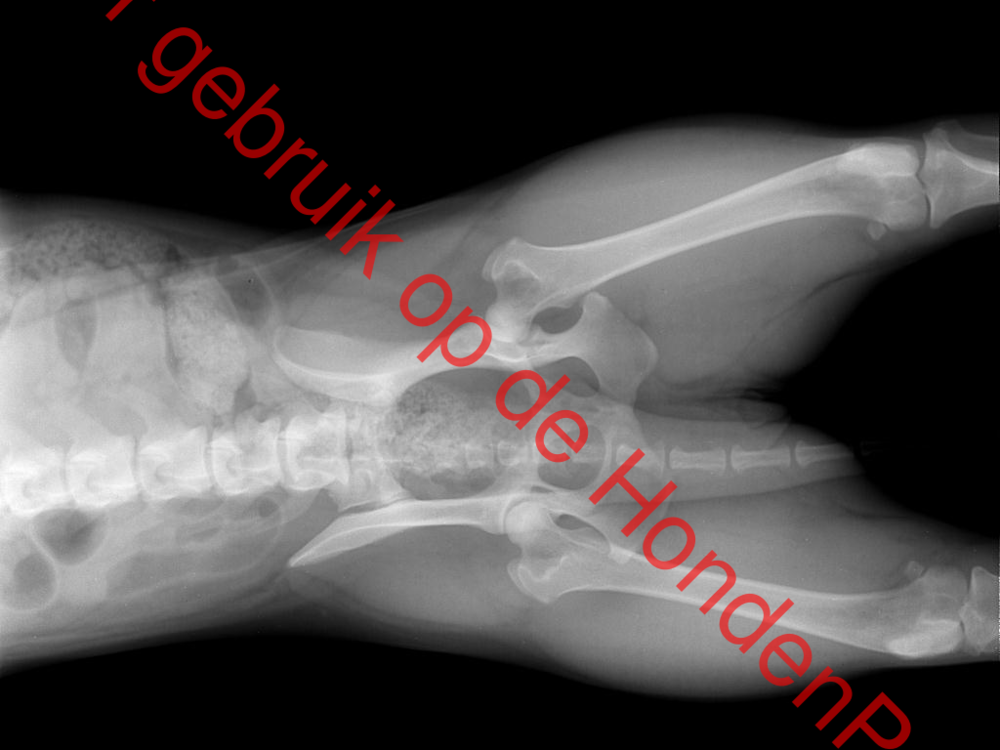

Tess is getest op schouders, knieën, heupen en heeft op alles goed getest er was geen probleem te zien.